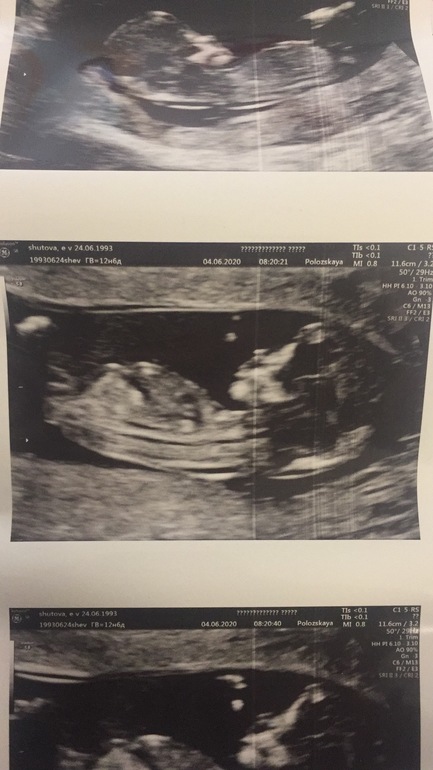

1 скрининг

Изменения и болезни во время БВсе, я прошла первый скрининг с кровью как положено))

Все отлично, малышка развивается.

Пол эта врач не предположила. Но по половому бугорку уже думаю все понятно) А что думаете вы?